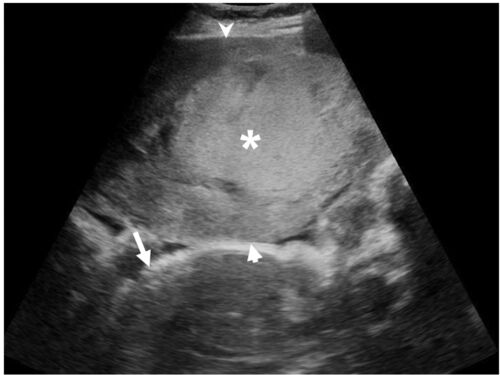

病歴/身体所見 ・36歳女性、妊娠37週 ・突然発症の腹痛と性器出血のためER受診 ・分娩前健診で羊水過少症の診断がされていた ・意識は清明、HR76bpm, BP87/52mmHg ・胎児心拍197bpm 検査 ・POCUS 高エコーな巨大なmass(*)が胎盤(短矢印)と子宮(矢頭)の…